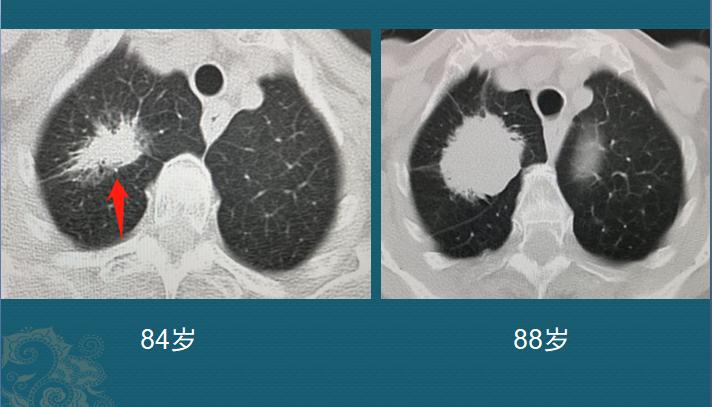

下面再看一位发展相对比较慢的肺癌:

这是一位84岁老太太,因为咳嗽、胸闷、偶尔胸痛,CT查出右肺腺癌,表现为混合磨玻璃密度,长径3.4cm。考虑到老人高龄,只做了止咳、止痛处理,今年已经4年了,肿块增大到4.3cm,并且完全变为实性密度,很幸运没有远处转移。